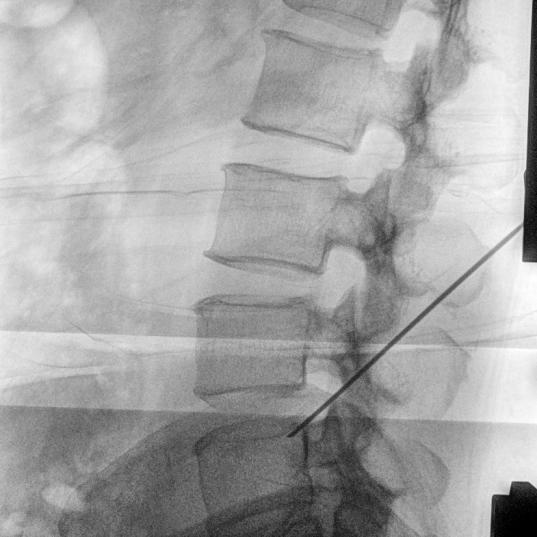

3智能设置 清晰影像 Apricus-C8000乐影C形臂应用了最新的IGZO探测器,具有优秀的低剂量性能,更加开阔的视野,以及对图像细节的精细雕刻。它搭载了有效区域达到23×23cm的动态平板探测器。

4精致细节 一目了然 丰富的细节,提高诊断准确性,清楚地看到每个解剖细节.Apricus-C8000独具匠心的影像链都能为您提供出色的细节丰富的高质量图像。

此次Apricus-C8000小C的成功安装,将为医院的骨科、疼痛科、介入科等科室提供强有力的技术支持,帮助医生更精准、更高效地完成诊疗工作,为患者带来更安全、更优质的医疗服务。未来,我们将继续与茶陵腰潞中医医院紧密合作,提供全方位的技术支持和服务,共同推动医疗事业的进步!